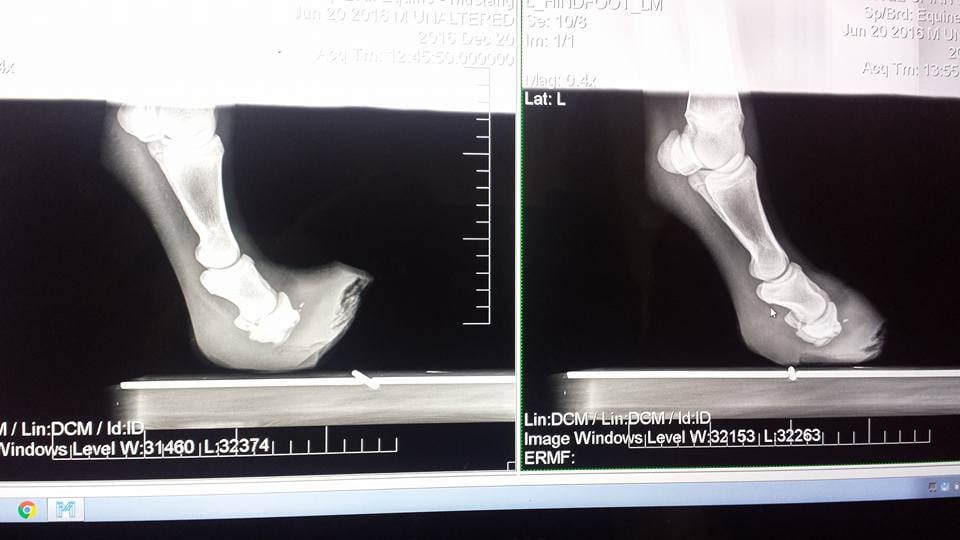

Hamilton’s first farrier appointment raised immediate concern: his hind feet weren’t just curled, they suggested severe founder or even bone death. Expecting the worst, we took him for radiographs — but the images revealed something entirely different. Hamilton hadn’t lost his coffin bones. He had never developed them.

Where the coffin bone (P3) should have been, there were only small nubs at the end of P2, and the wings of the coffin bone — the structures that give the hoof its shape and support — had simply never formed. On the X-rays, you could see the faint points where bone should have attached, like a blueprint nature had drafted but never completed.

Because he wasn’t showing the kind of pain that degenerative disease would cause, the results left us with more questions than answers. We knew his case needed expert eyes. Shortly after weaning, Hamilton traveled alone to Cody, Wyoming, to see Dr. Ted Vlahos, a leading specialist in limb abnormalities and complex lameness. After reviewing the films and examining him in person, Dr. Vlahos confirmed what the radiographs hinted at: Hamilton’s condition wasn’t just rare — it was unprecedented. He told us Hamilton was the first documented case of bilateral congenital failure of the coffin bones to develop.